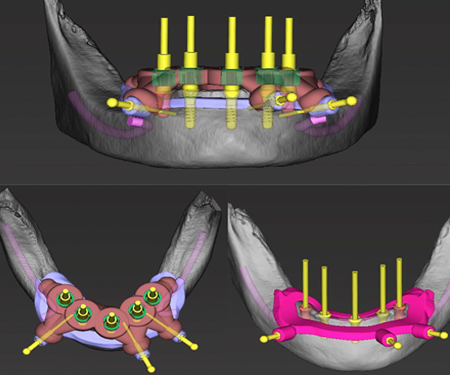

种植修复

打印-种植钴铬瓷牙

打印-种植桥